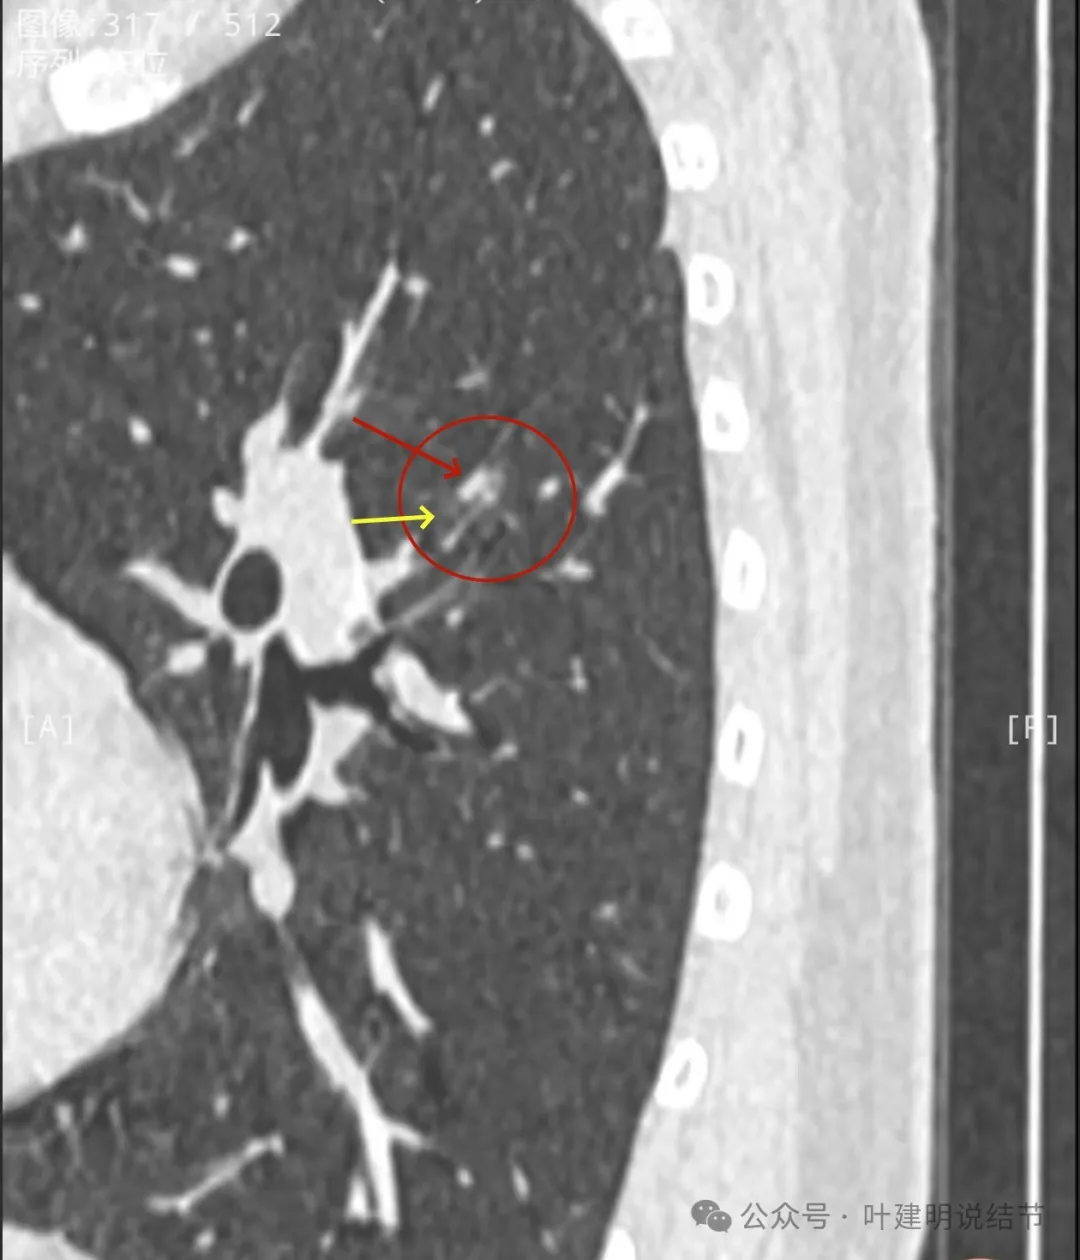

矢状位沿着叶间裂略显长条状,靠叶间裂侧密度较高,边上的低密度管道状像细支气管,横断面的上小空泡是扩张的细支气管吗?矢状位上看收缩力不明显。